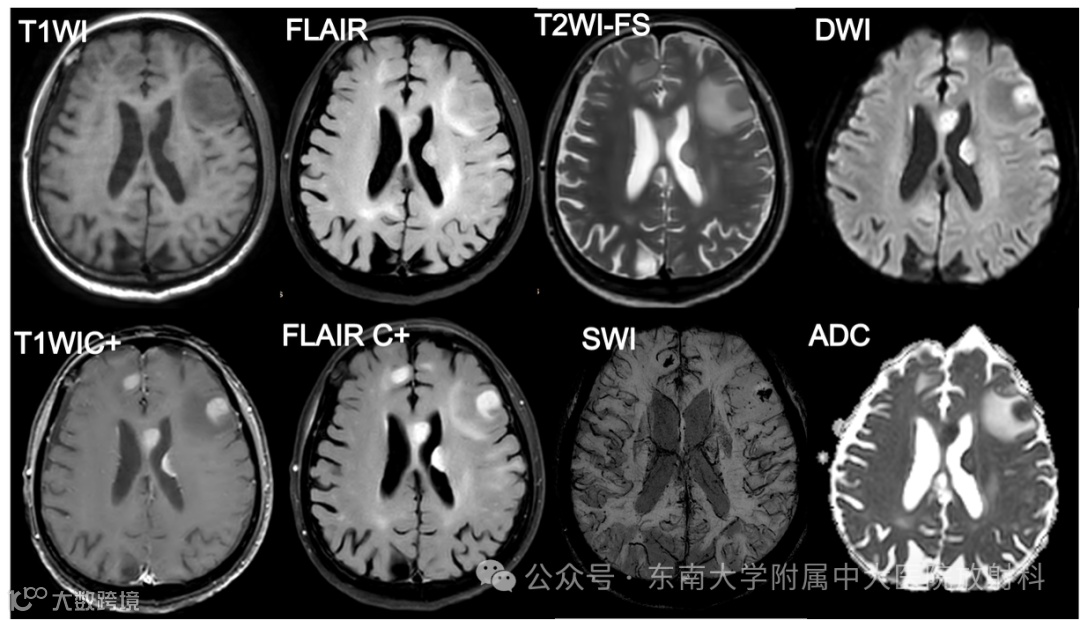

影像号:1217119452 2025-09-08 盆腔MR平扫

影像学表现